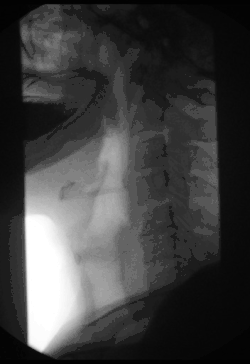

Fluoroscopy (/flʊəˈrɒskəpi/)[1], informally referred to as "fluoro", is an imaging technique that uses X-rays to obtain real-time moving images of the interior of an object. In its primary application of medical imaging, a fluoroscope (/ˈflʊərəˌskoʊp/)[2][3] allows a surgeon to see the internal structure and function of a patient, so that the pumping action of the heart or the motion of swallowing, for example, can be watched. This is useful for both diagnosis and therapy and occurs in general radiology, interventional radiology, and image-guided surgery.

Surgical fluoroscopy